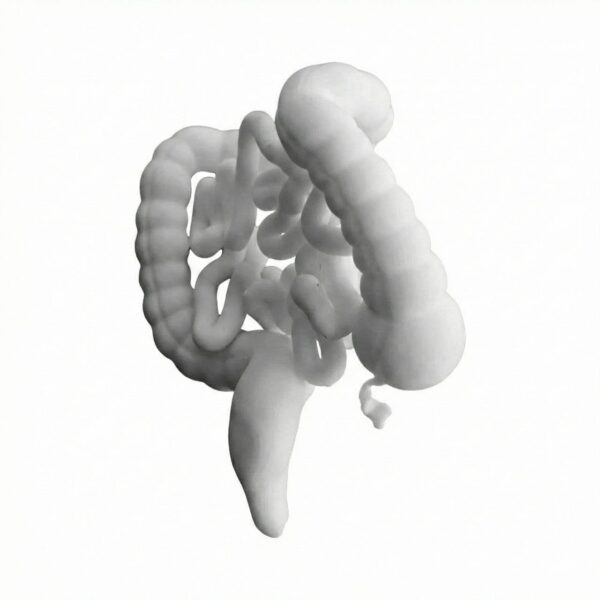

Visualisez l’anatomie digestive en 3D avec cette reproduction fidèle du système intestinal. Ce modèle didactique permet de distinguer clairement le côlon de l’intestin grêle, idéal pour l’enseignement ou la démonstration patient.

| Modèle du Tractus Intestinal : Gros Intestin et Intestin Grêle | 1 6500 د.ج |